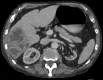

Pyogenic liver abscess

Pyogenic liver abscess has a variable clinical presentation. Its management requires input from several disciplines and is often coordinated by a gastroenterologist. This review examines demographics, clinical presentation, aetiology, diagnosis and prognosis; a suggested management approach, including antibiotic selection, radiological intervention and indications for surgery, is offered from a physician's perspective.